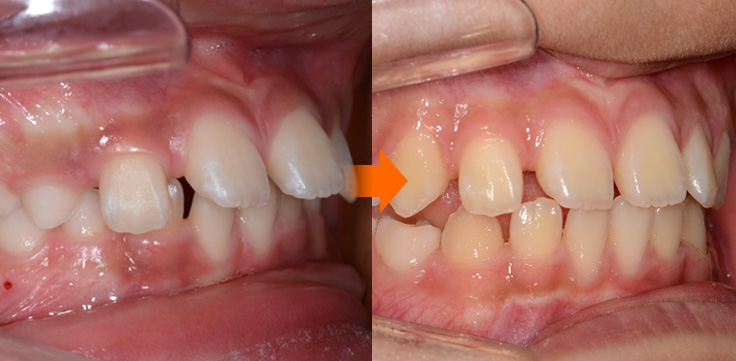

반대교합(주걱턱 예방)

주걱턱

주걱턱, 조기에 예방할 수 있습니다.

페이스마스크를 활용한 악정형 장치로 앞니 반대교합을 개선하고, 주걱턱을 미리 예방할 수 있습니다. 적절한 시기의 예방교정을 통해 자연스럽고 건강한 치열로 성장할 수 있도록 도와주었습니다.

• 주증상

전치부 반대교합

• 치료기간

약 6개월

• 부작용

치아표면의 탈회, 치은 부종, 치근흡수 등의 부작용이 있을 수 있습니다.